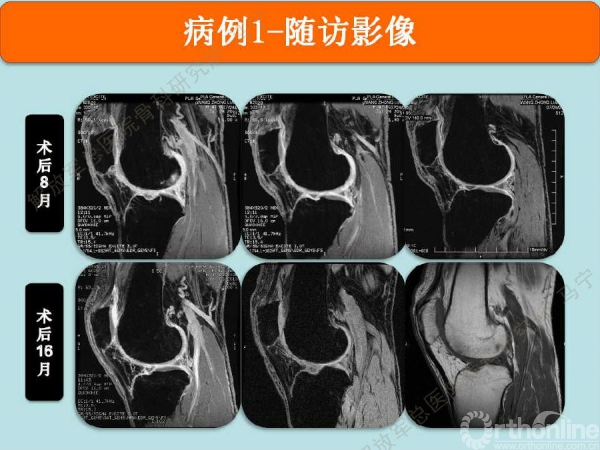

术后8个月修复区的软骨厚度恢复理想,软骨下骨水肿信号不明显。术后16个月复查修复区的软骨没有太明显的变化。

患者是一个建筑公司的工长,每天要走很多路,对目前的效果很满意。